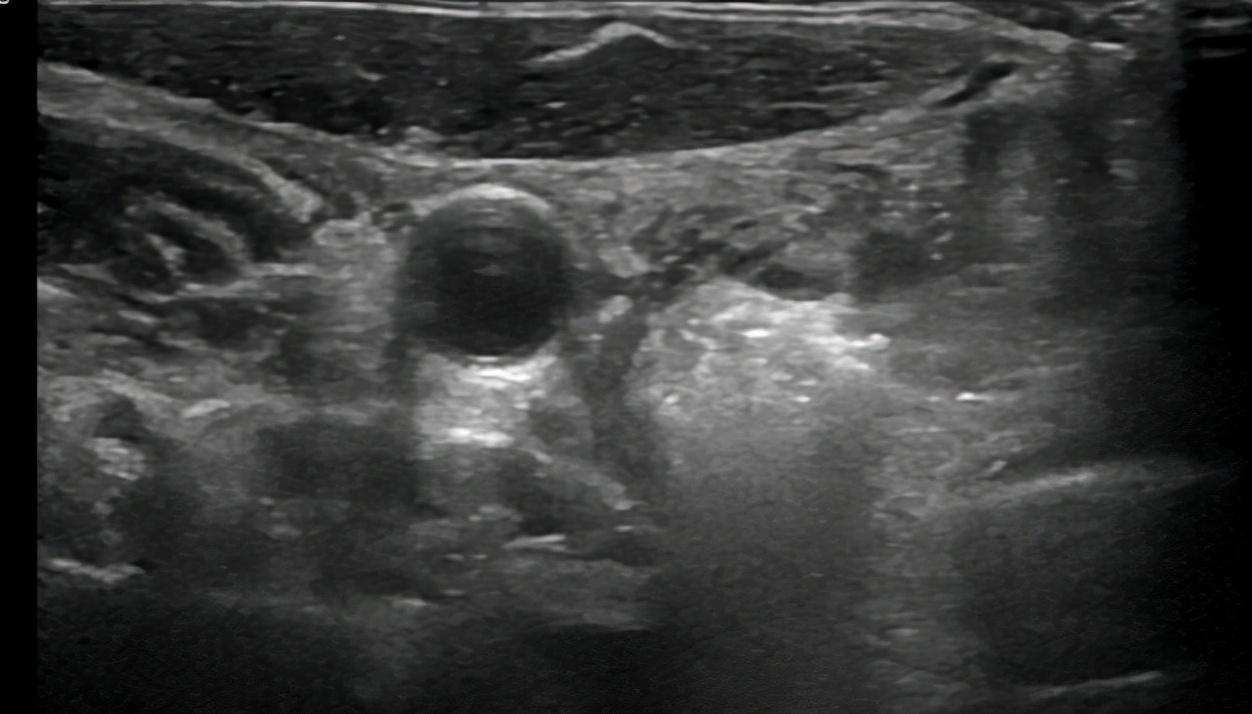

微波消融针穿刺进行结节内施行消融。

超声造影评价消融效果。

消融针穿刺

消融开始

消融中

消融结束

超声造影显示消融完全